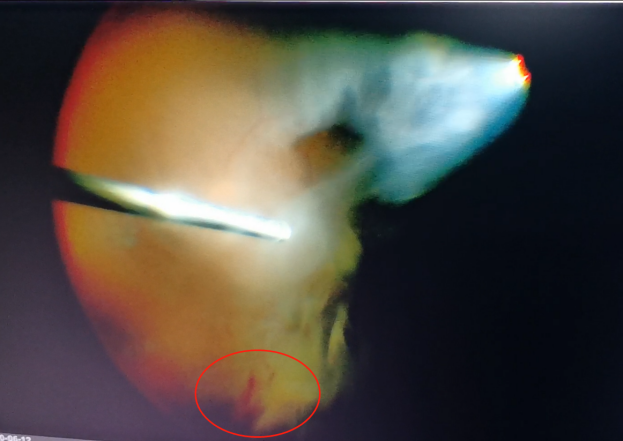

(左為玻璃體切割術(shù)中,明顯可見有積血;右為激光治療后的眼底)

術(shù)后第二天視力檢查時,程先生經(jīng)過手術(shù)的左眼矯正視力已經(jīng)恢復(fù)為1.0,眼前也不再有“黑片片”遮擋視線?;謴?fù)了清晰“視界”的程先生,開心地自己在病房外來回溜達。